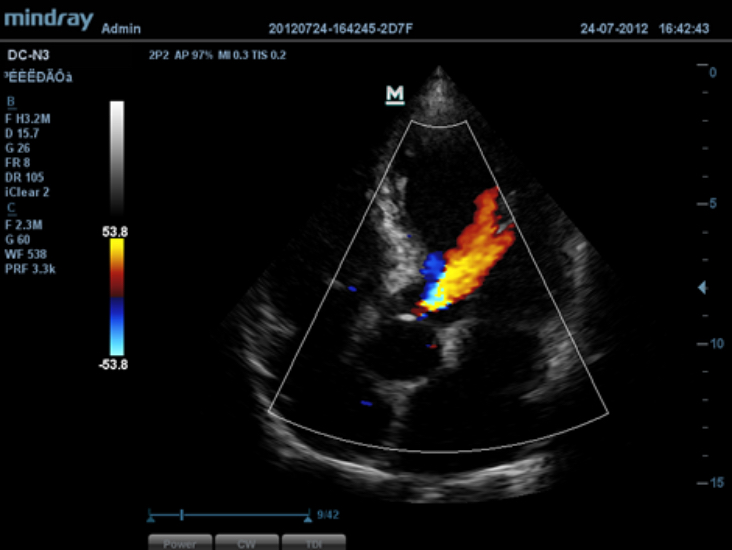

El DC-N3 PRO es un sistema Doppler a color con todas las funciones que satisface sus necesidades de diagnĂłsticos mĂĄs rĂĄpidos, confiables y precisos. Gracias al mejor rendimiento, eficacia y dise?o de su clase, puede estar seguro de que obtendrĂĄ una experiencia de ecografĂa excepcional. Con su dise?o compacto, fĂĄcil de usar y ergonĂłmico, se puede mover, usar y ubicar segĂșn sus requisitos sin lĂmites.

PSH? (Phase Shift Harmonic Imaging)

ImĂĄgenes de armĂłnicos purificados con desplazamiento de fase para una mejor resoluciĂłn de contrastes que proporciona imĂĄgenes mĂĄs nĂtidas con excelente resoluciĂłn y menos ruido.